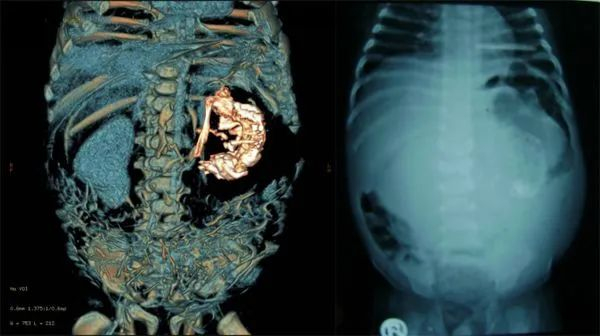

在彩超和3D/4D超声影像图上,帕拉·萨维德拉医生发现,图中充满液体的区域中,实际上含有一个非常小的胎儿;同时,还有一条独立脐带将小的胎儿连接在大的双胞胎的肠子上,并为小胎儿供血。

“我告诉了那位母亲,她的反应是——什么?不,这不可能!” 帕拉·萨维德拉医生说,“在我逐步解释后,她才明白。” 超声扫面的结果显示出位于子宫内的胎儿腹中,有一个正在成形的双胞胎小胎儿 | Dr. Miguel Parra-Saavedra